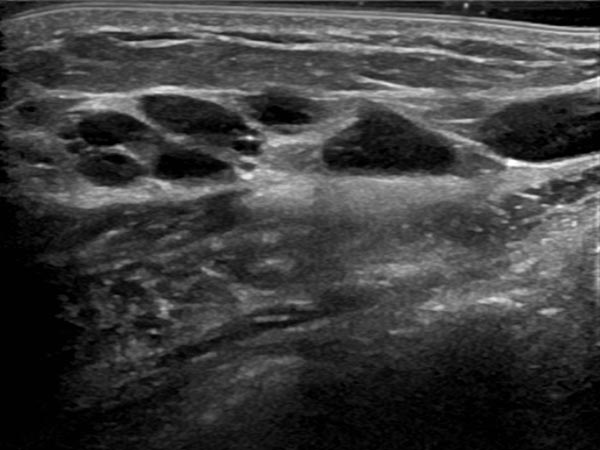

Ultrasound of the abdominal wall, a little further caudally. Here, the cystic parts of the lymphatic malformation are smaller. However, the lesion is still extraperitoneal in the abdominal wall.